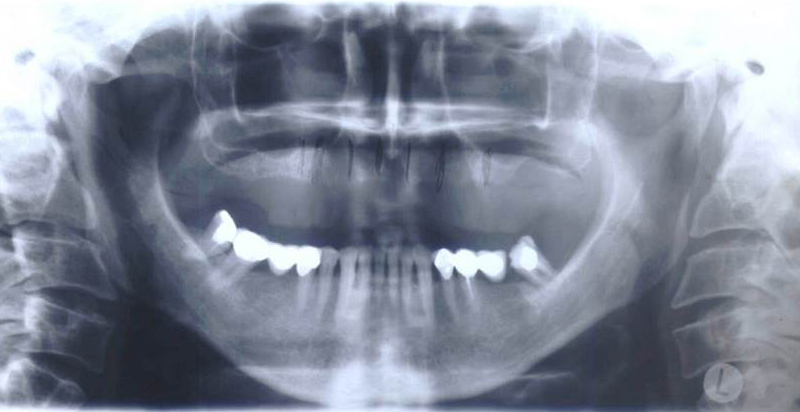

Při ztrátě molárů a premolárů v horní čelisti a jejich náhradě implantáty se často setkáváme s nedostatečnou vertikální nabídkou kosti pod čelistní dutinou, často doprovázenou i nedostatečnou horizontální nabídkou a sníženou kvalitou kosti

(v oblasti 2. premoláru v 50%, v oblasti moláru až v 80% případů nedostatečná kostní nabídka)

Od roku 1985 je tento problém řešen augmentační operací nazývanou sinus lift.

Jedná se o vyzvednutí membrány, která čelistní dutinu vystýlá, pod vyzvednutou membránou vznikne kapsa, kam se umístí augmentační materiál, do kterého se zavedou implantáty.